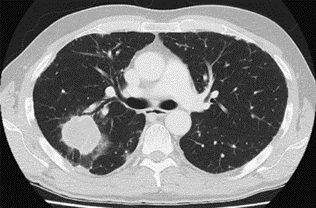

- CECT thorax was done which showed a mass lesion in the posterior segment of the right upper lobe (Figure 1).

Figure-1 Mass lesion in the posterior segment of the right upper lobe